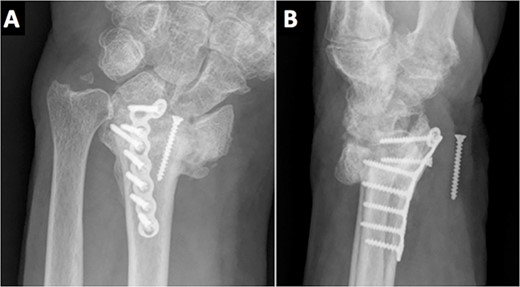

An 84-year-old, right-handed man attended the emergency room for the pain and swelling of his left wrist after a fall over his outstretched arm from a standing height. An X-ray was performed, showing an intra-articular comminuted fracture on the left distal radius, classified as 23-C3 according to the AO classification (Fig. 1). A cast was placed in the first place; meanwhile, the final treatment was decided.

The radiological images in the emergency department showed a comminuted intra-articular displaced fracture of the distal radius.